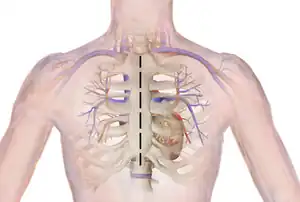

Ross procedure, also known as pulmonary autograft, is a type of aortic valve replacement to treat severe aortic valve disease, usually in children and young adults with a bicuspid aortic valve.[2] It involves removing the diseased aortic valve, situated at the exit of the left side of the heart (where the aorta begins), and replacing it with the person's own healthy pulmonary valve (autograft), removed from the exit of the heart's right side (where the pulmonary artery begins).[3] To reconstruct the right sided exit, a pulmonary valve from a cadaver (homograft), or a stentless xenograft, is used to replace the removed pulmonary valve.[2][lower-alpha 1] Compared to a mechanical valve replacement, it avoids the requirement for thinning the blood, has favourable blood flow dynamics, allows growth of the valve with growth of the child and has less risk of endocarditis.[2]

Before the operation, preparations include transthoracic echocardiography and measurements of the ascending aorta and the pulmonary valve.[10] Under general anaesthesia, the chest is cut open in the midline.[5] The heart and aorta are exposed before the heart is temporarily stopped and its function taken over cardiopulmonary bypass.[5] Subsequent steps include removing the diseased aortic valve and mobilizing the coronary arteries, followed by harvesting and preparing the person's own healthy pulmonary valve, before implanting it within the left ventricular outflow tract, the exit of the left side of the heart (where the aorta begins).[2][10] Then the coronary artery is reimplanted, before the pulmonary homograft is implanted in the right ventricular outflow tract, the exit of the heart's right side (where the pulmonary artery begins).[2][10] The pulmonary autograft is joined with the ascending aorta.[2][10]